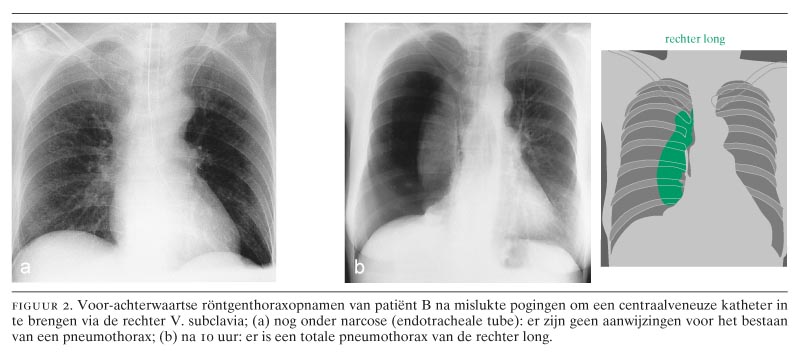

Patiënt B, een 62-jarige vrouw, was opgenomen met buikklachten op basis van een ileus. Zij was bekend wegens een ‘short bowel’-syndroom bij de ziekte van Crohn, waarvoor reeds diverse darmresecties waren verricht. In verband met het trage herstel van haar buikklachten werd besloten tot het inbrengen van een centraalveneuze katheter voor parenterale voeding. In het verleden had patiënte reeds meerdere centraalveneuze katheters gehad, zowel in de linker als in de rechter V. subclavia. Na een mislukte poging tot plaatsing van een katheter links, onder lokale anesthesie, werd een echodoppleronderzoek verricht van de beide Vv. subclaviae. Dit toonde obliteratie van de linker V. subclavia. Rechts was er een normale doorgankelijkheid. Derhalve werd een poging gedaan de rechter V. subclavia aan te prikken. Op verzoek van patiënte geschiedde dit onder algehele anesthesie. In eerste instantie werd arterieel gepuncteerd. Daarna werd met behulp van een echodopplerapparaat de V. subclavia gelokaliseerd en gecanuleerd. Het bleek echter niet mogelijk om een voerdraad op te voeren. Hierop werd besloten te stoppen en een lieskatheter in te brengen volgens de Seldinger-methode. Dit verliep ongecompliceerd. Een liggende röntgenfoto van de thorax toonde geen afwijkingen, in het bijzonder geen pneumothorax (figuur 2), ook niet na revisie. Tien uur later werd patiënte echter benauwd. Een nieuwe röntgenfoto toonde een totale collaps van de rechter long (zie figuur 2). Patiënte heeft direct een thoraxdrainage gekregen. Na enkele dagen kon deze thoraxdrain worden verwijderd. Patiënte herstelde zonder verdere complicaties.